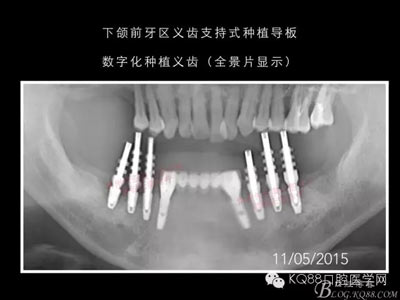

下面的種植病例是為患者提供全口牙齒治療修復(fù)完整過(guò)程的下頜部分,我們門(mén)診和患者共同配合下目前取得了較好的修復(fù)效果,即將開(kāi)始的上頜牙齒治療修復(fù)過(guò)程仍然艱辛。